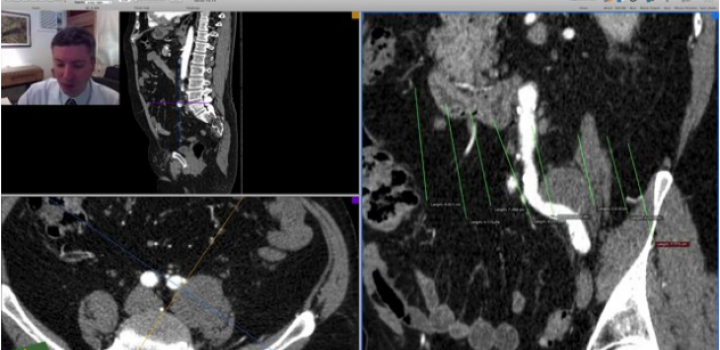

O 3D Curved MPR é a ferramenta que permite fazer o centerline manual no OsiriX.

É importantíssimo entender o 3D-MPR antes de passar para o 3D Curved MPR.